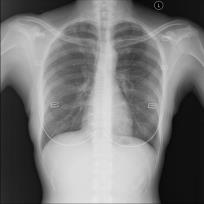

Chest X-ray (CXR) is the most typical radiological exam for diagnosis of various diseases. Due to the expensive and time-consuming annotations, detecting anomalies in CXRs in an unsupervised fashion is very promising. However, almost all of the existing methods consider anomaly detection as a One-Class Classification (OCC) problem. They model the distribution of only known normal images during training and identify the samples not conforming to normal profile as anomalies in the testing phase. A large number of unlabeled images containing anomalies are thus ignored in the training phase, although they are easy to obtain in clinical practice. In this paper, we propose a novel strategy, Dual-distribution Discrepancy for Anomaly Detection (DDAD), utilizing both known normal images and unlabeled images. The proposed method consists of two modules, denoted as A and B. During training, module A takes both known normal and unlabeled images as inputs, capturing anomalous features from unlabeled images in some way, while module B models the distribution of only known normal images. Subsequently, the inter-discrepancy between modules A and B, and intra-discrepancy inside module B are designed as anomaly scores to indicate anomalies. Experiments on three CXR datasets demonstrate that the proposed DDAD achieves consistent, significant gains and outperforms state-of-the-art methods. Code is available at https://github.com/caiyu6666/DDAD.